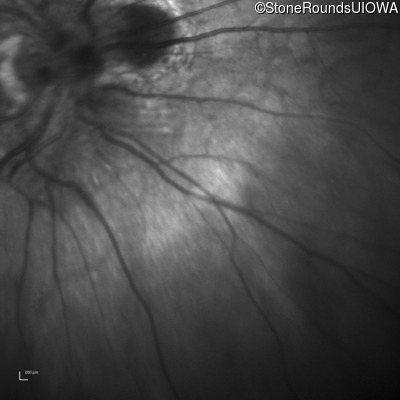

Optical Coherence Tomography - Right - 20/2000

Exemplar / OCT Stack